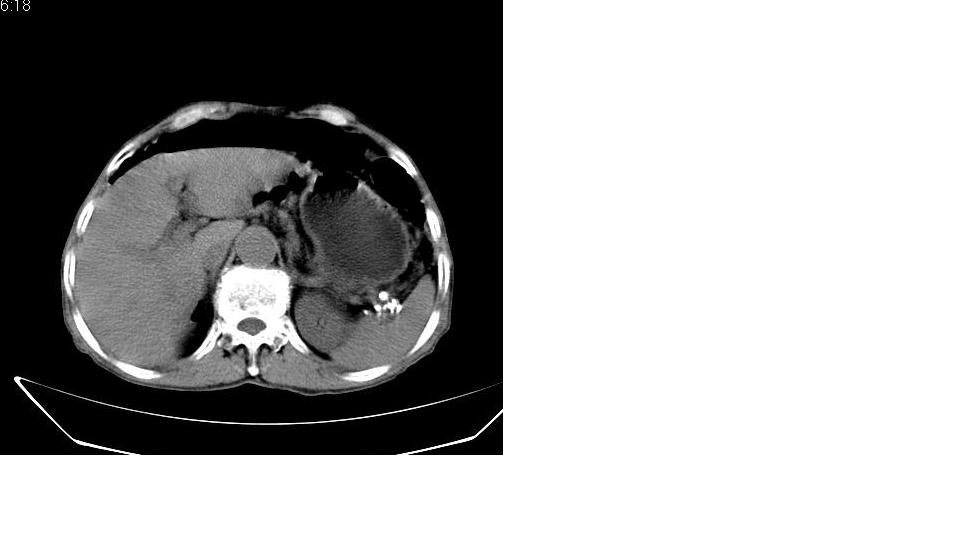

男,76岁,上腹部疼二天来就诊,彩超提示肝左叶占位,随后做上腹部ct平扫,今天做上腹部ct增强扫描,手工推药,效果不好,请谅解。

肝左叶s4肿块强化形式大概是:慢进慢出,逐渐强化----考虑血管瘤/腺瘤?{动脉期应更提前扫}。

肝右叶前段hcc

1)肝右叶前段低密度灶,不排除肝癌可能;建议查afp。2)右肾上极囊肿。

肝内胆管积气扩张,胆囊增大,肝右前叶低密度灶,逐渐强化,一元论,胆系感染,局限性肝脓肿;右肾囊肿。

考虑肝s4段肝脓肿可能?未排除肝癌。右肾上极囊肿。